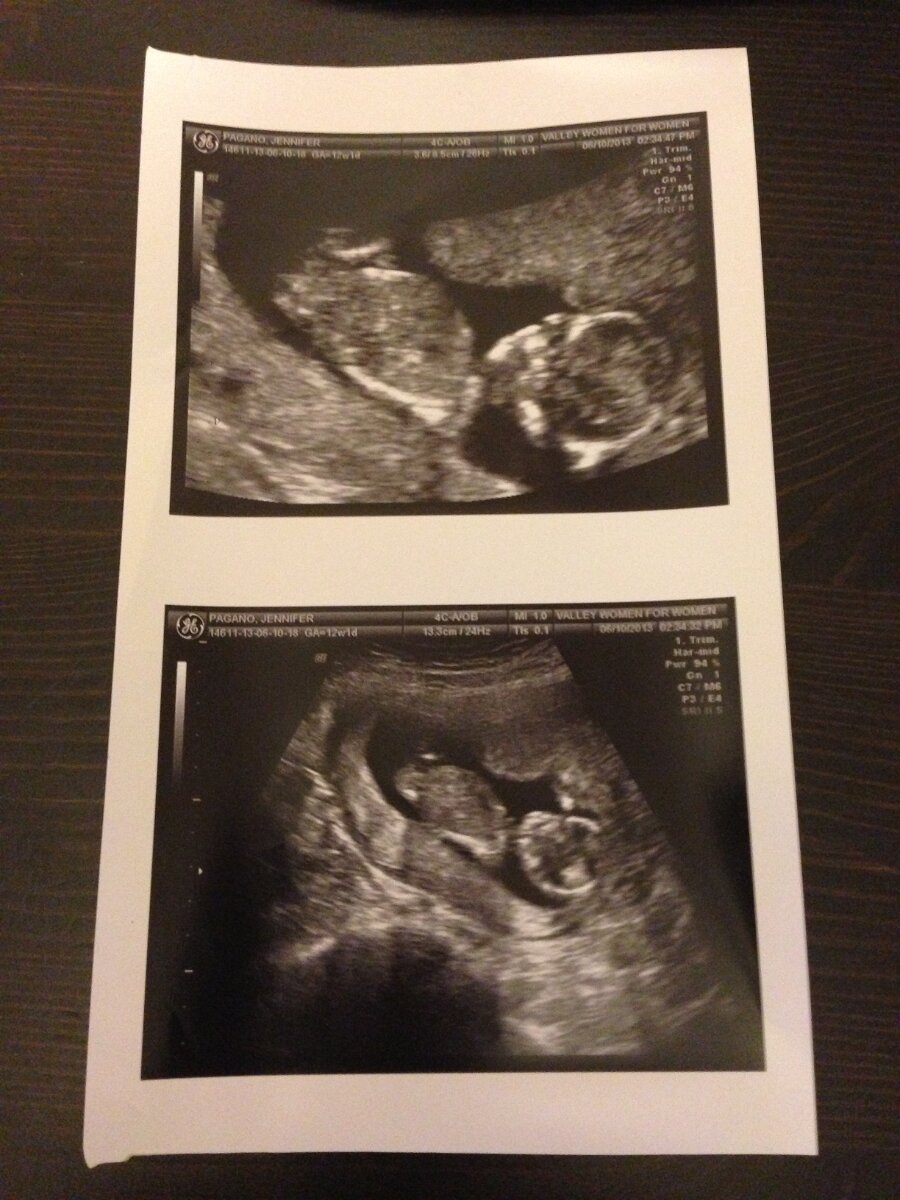

2013-06-10

June 10th

Our Baby